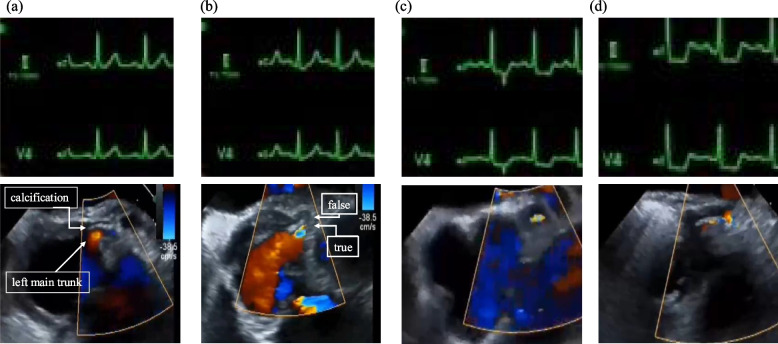

Case presentation: A 77-year-old man underwent emergency aortic arch replacement for acute type-A aortic dissection. Intraoperative transesophageal echocardiography (TEE) initially showed no coronary involvement. However, ST-segment elevation and new hypokinesia appeared post-repair. TEE identified progressive left main coronary artery stenosis. Coronary angiography confirmed severe stenosis, leading to urgent coronary artery bypass grafting. The patient recovered well and was discharged on postoperative day 33.